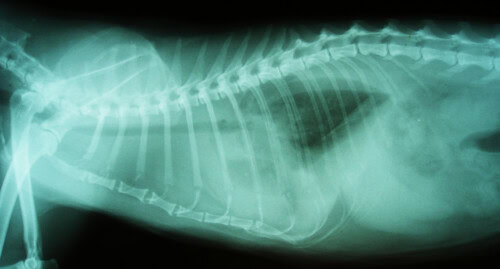

La difficulté respiratoire amène à réaliser en premier lieu des radiographies thoraciques, qui mettent en évidence un épanchement pleural massif.

Photo 5 : Visualisation radiographique de l’épanchement pleural